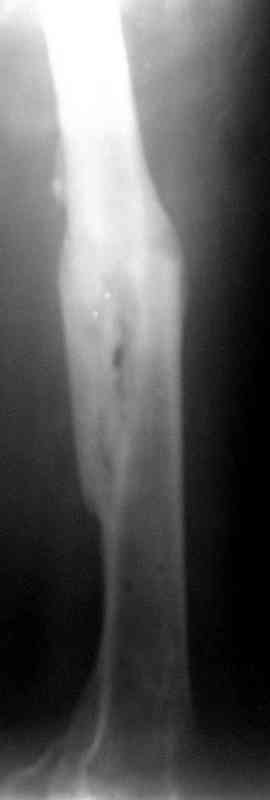

Фиксаторы удалены через 12 месяцев после операции, выполненной по поводу замедленной консолидации перелома бедра с его укорочением.

Спасибо! Истинно мастерская работа. Представляю как счастлив пациент исходом этой истории.

На финальных снимках видно - сращение прям таки железное. Если Вы не устали отвечать, осмелюсь задать еще вопрос - что-то принимал пациент в целях ускорения сроста (кальций, режим питания). Интересны также вопросы восстановления функций конечности - в какой период были рекомендованы группы упражнений для восстановления основных групп мышц?